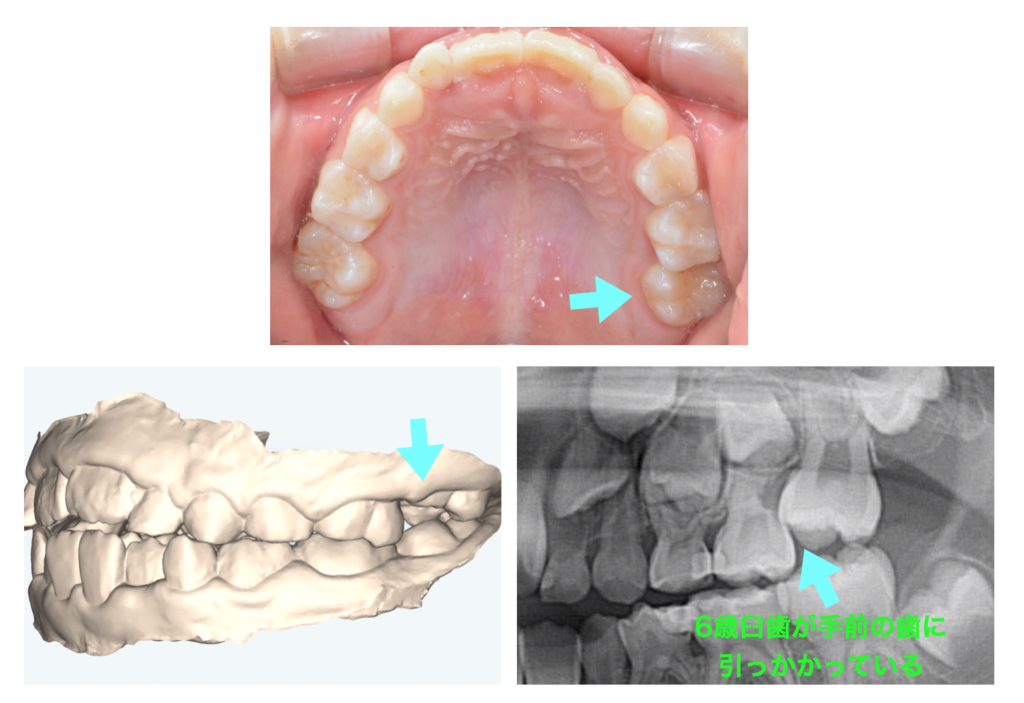

小児矯正 まっすぐに生えない大臼歯をリンガルアーチで誘導

| 主訴 | 7歳11ヶ月女児 かかりつけで、左上の歯がちゃんと生えてこないと指摘された。 |

| 治療内容 | 左上第一大臼歯が左上第二乳臼歯に引っかかっており、萌出障害が生じていた。このままでは、第二乳臼歯が通常より早く抜けてしまうことと、第一大臼歯が手前に出て、今後の永久歯配列のスペースが失われ、歯並びに悪影響が出ることが予想された。リンガルアーチを装着して、左上第一大臼歯にボタンを設置し、ゴムを用いて奥側に牽引し、引っかかりを解除する方針とした。牽引開始から特に問題なく経過し、5週間後に装置を除去、その後問題なく萌出を完了した。 |